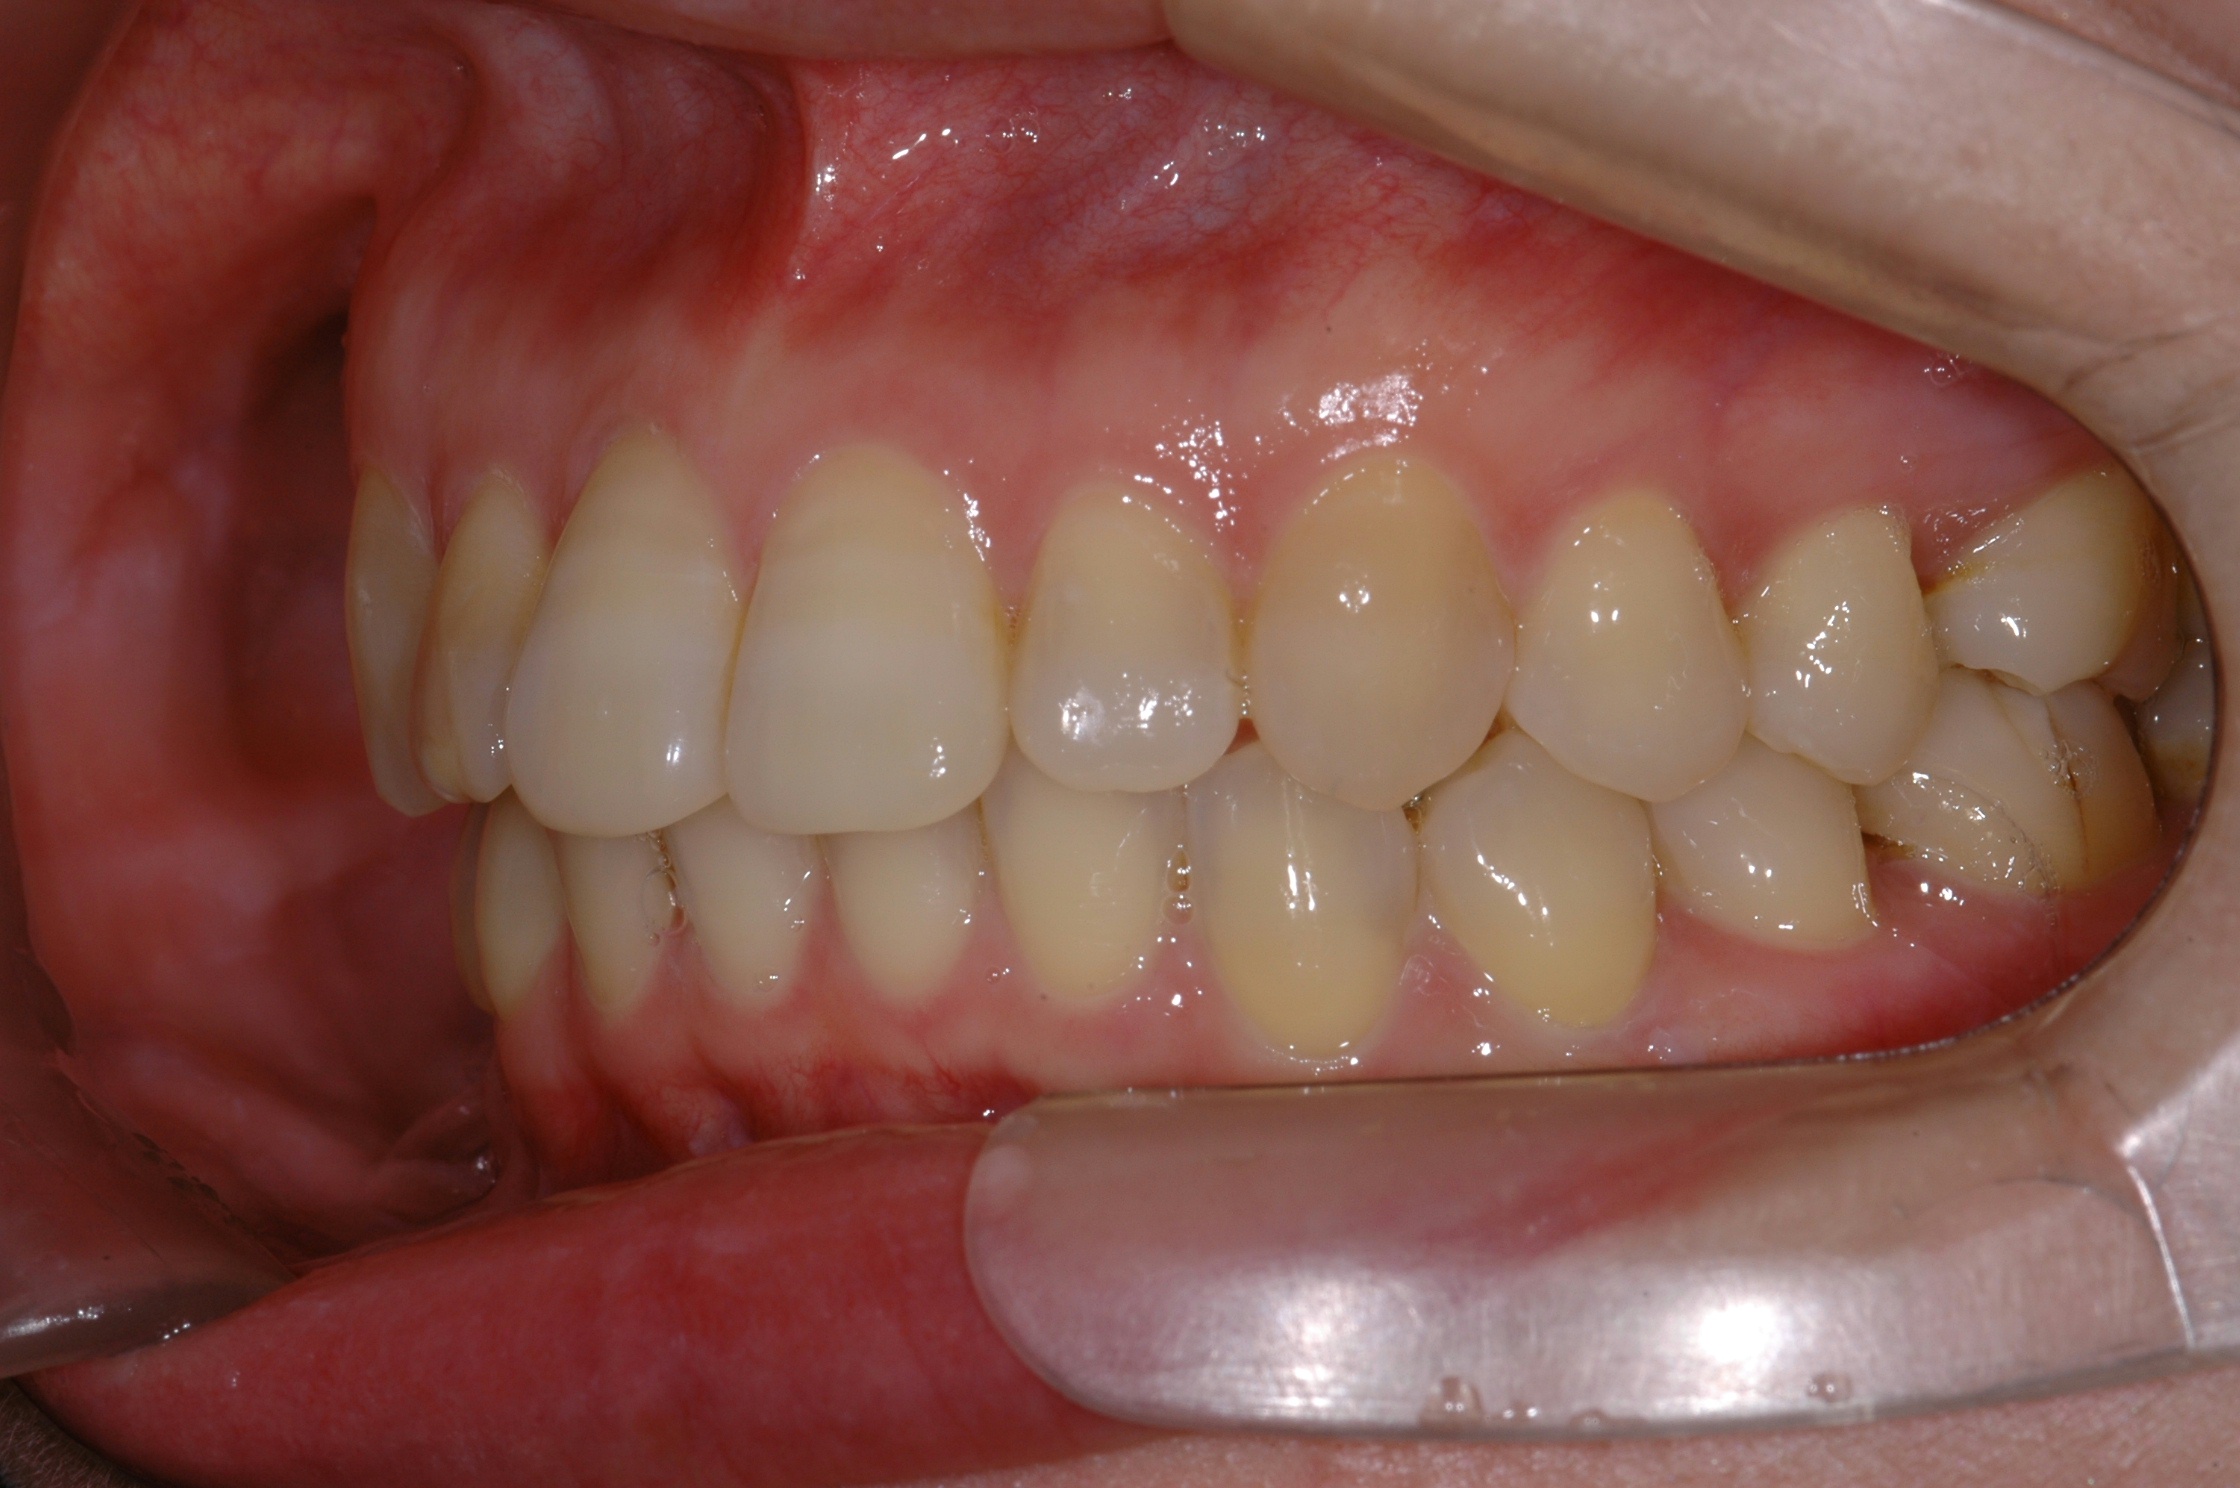

치료 후 사진입니다.